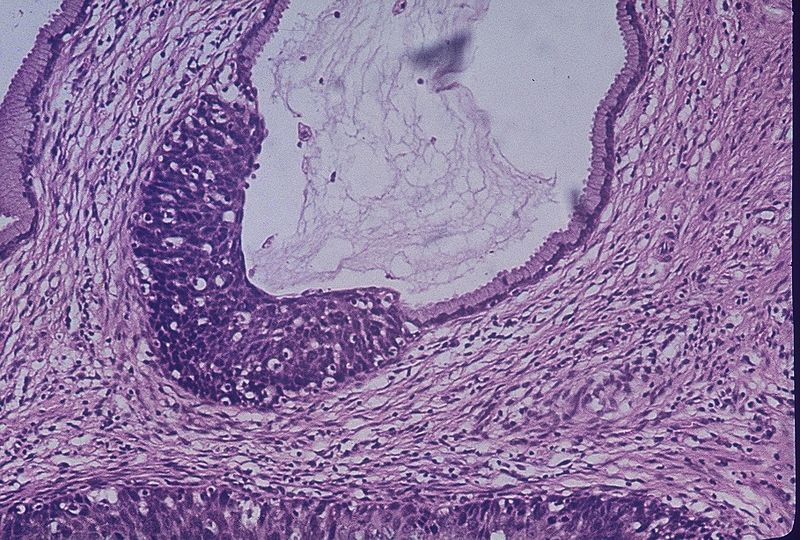

Colonic Polyps

Clinical DescriptionA-B. No polyps in the colon of unaffected member with normal histology (III-2). C-D. No polyps in the rectum of unaffected member with normal histology (III-2). E-F. Polyps in the colon, Cancer invading in the submucosa in proband (III-1); G-H. Polyps of rectum showing Low grade intraepithelial neoplasia (dysplasia), the gland of local lesion showing High grade intraepithelial neoplasia (dysplasia) in proband (III-1). I-J. Polyps of colon showing High grade intraepithelial neoplasia (dysplasia) in III-4; K-L. Polyps of rectum, adenocarcinoma in III-4. M-N. Polyps of colon is Low grade intraepithelial neoplasia (dysplasia), the gland of local lesion is High grade intraepithelial neoplasia (dysplasia) in III-5; O-P. Polyps of rectum are Low grade intraepithelial neoplasia (dysplasia) in III-5; Q-R. Polyps of colon are Low grade intraepithelial neoplasia (dysplasia) in III-7; S-T. Polyps of rectum are Low grade intraepithelial neoplasia (dysplasia) in III-7; U-V. Polyps of colon are High grade intraepithelial neoplasia (dysplasia) in III-9; W-X. Polyps of rectum are Low grade intraepithelial neoplasia (dysplasia) in III-9. A novel pathogenic large germline deletion in adenomatous polyposis coli gene in a Chinese family with familial adenomatous polyposis. Oncotarget. Not Altered. CC.